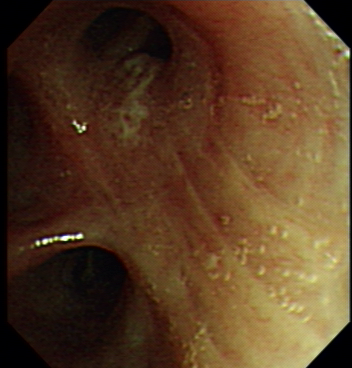

Once patients are suspected to have lung cancer or TB with X-ray or CT, bronchoscopy is followed-up from radiological imaging. Bronchoscopy is used as one of the invasive tool to directly detect the disease since 1960s [4]. Fig. 1 shows an example of normal tissue, TB and cancer. In bronchoscopy, usually we can observe that invasive TB, the lumen surface suffers from inflammatory change with hyperemia, edema and ulceration. Lung adenocarcinomas grow extraluminally and lead to lumen stenosis without affecting mucosal surface of lumen. Therefore, the mucosal surface of lumen is relatively smooth. However, squamous lung cancers always form intruding nodules and are difficult to be differentiated from TB granuloma visually. Computational aid is therefore needed in bronchoscopy, especially for lesion discrimination and targeting. Accurate targeting the disease area could significantly reduce the biopsy trauma and increase diagnostic accuracy [5].

Figure 1: A bronchoscopy image of normal (a), TB (b) and cancer (c)